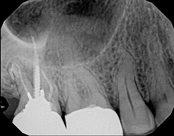

Non-surgical root canal treatment:

Before

After

6-month follow-upThe patient presented with mild pain, a cavity, and a broken filling was evident. After performing diagnostic testing, the diagnosis was: irreversible pulpitis, symptomatic periradicular periodontitis. Root canal therapy was done and the tooth healed well and is still functioning.